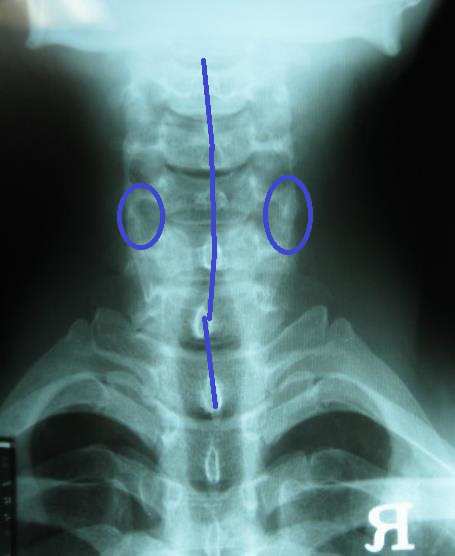

진단 : 요통과 관련한 척추문제는 해결한 상태였으나 어깨 검사를 해보니 좌측 어깨의 회전 범위가 많이 감소된 상태였고 근육적인 문제가 약간 보이긴 하나 그리 심하지는 않은 상태였습니다. 다시 척추문제를 재검 해 보니 흉추의 문제가 남아 있었습다. 이 후 1-2회 흉추 치료를 하였고 치료 후 어깨 운동 범위가 많이 개선되었다고 평상시 본인은 어깨가 아픈지 몰랐는데 치료 받고 보니 어깨가 많이 가벼워졌다고 좋아하셨습니다. 수 개월 후 발목 염좌로 내원하였고 어깨 문제를 재검해보니 별 문제는 없었으며 골프도 시원스럽게 잘 쳐진다고 만족해 하셨습니다.